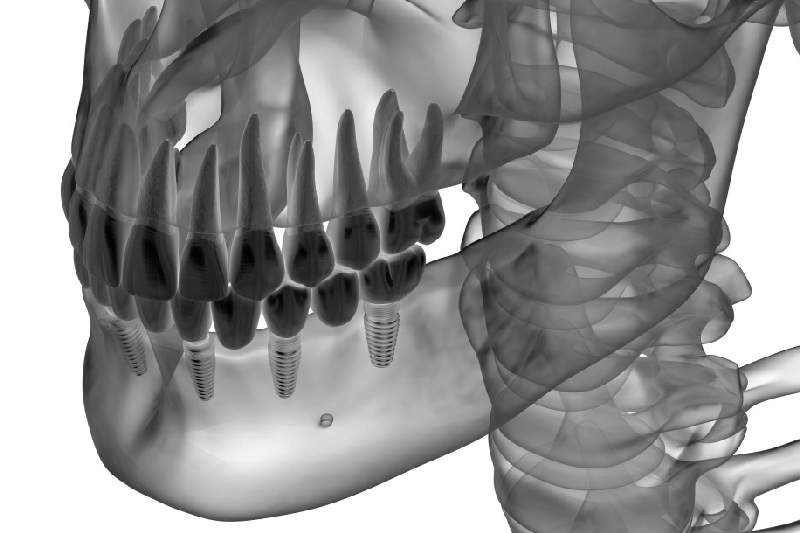

Τα οδοντικά εμφυτεύματα αποτελούν εξαρτήματα τα οποία τοποθετούνται χειρουργικά στο οστό της γνάθου με σκοπό την αντικατάσταση ενός ή περισσότερων ελλειπόντων δοντιών. Τα εμφυτεύματα είναι τεχνητά υποκατάστατα των ριζών και έχουν πλήρη λειτουργικότητα όπως τα φυσικά δόντια. Με τα εμφυτεύματα επαναφέρουμε στο στόμα μας την αίσθηση που είχαμε πριν χάσουμε τα δόντια μας, αποκτούμε ξανά ορθή άρθρωση κατά την ομιλία, τέλεια αισθητική εμφάνιση, ενώ παράλληλα αποτελούν εγγυημένα τη μακροβιότερη και πιο αξιόπιστη λύση.

Τα οδοντικά εμφυτεύματα τοποθετούνται σε ασθενείς που έχουν καλή οστική μάζα. Επειδή όμως η οστική μάζα κάθε ατόμου μετά από απώλεια δοντιών μπορεί να αλλοιωθεί, απαραίτητη είναι η λήψη υπολογιστικής τομογραφίας κωνικής δέσμης (CBCT) προκειμένου να βρεθεί το καλύτερο δυνατό θεραπευτικό σχέδιο. Το ποσοστό επιτυχίας των εμφυτευμάτων αγγίζει το 98%.

Κάθε σχέδιο θεραπείας είναι μοναδικό. Δεν είναι απαραίτητο να τοποθετηθεί ένα εμφύτευμα για κάθε δόντι που έχει χαθεί. Τόσο στην άνω όσο και στην κάτω γνάθο είναι δυνατόν να αντικατασταθούν όλα τα δόντια με μια ολική σταθερή οδοντοστοιχία που θα στηρίζεται σε 6 εμφυτεύματα για κάθε γνάθο.

- Χειρουργική τοποθέτηση του οδοντικού εμφυτεύματος.